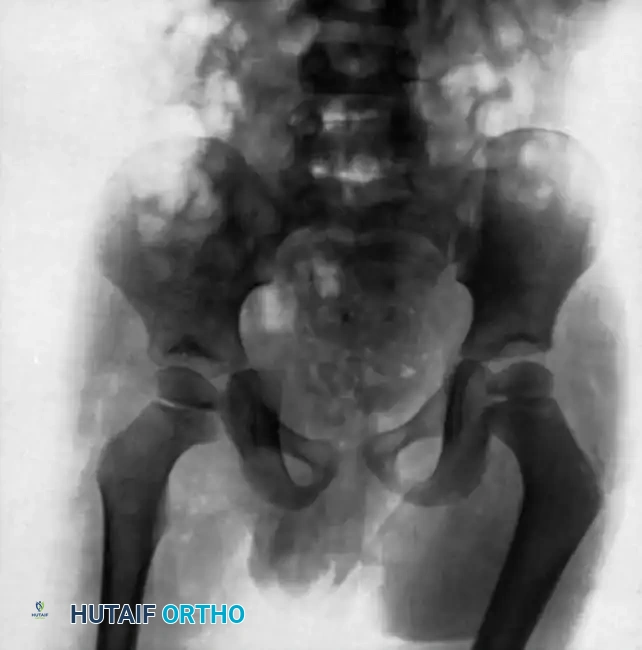

The Hip and Pelvis

Tuberculosis of the hip frequently affects children and young adults. The disease begins in the acetabular roof or the femoral head, rapidly progressing to joint space narrowing and severe destruction. A classic late-stage presentation is the "wandering acetabulum," where superior and medial migration of the femoral head occurs due to progressive bone loss.

In cases of severe destruction, nonoperative management leads to painful, fibrous ankylosis in a non-functional position (flexion, adduction, and internal rotation). Surgical intervention involves radical debridement. In modern practice, a two-stage total hip arthroplasty (THA) is often favored over hip arthrodesis to maintain mobility, provided the infection is medically cleared.

Pelvic and sacroiliac (SI) joint tuberculosis often presents with lower back pain radiating to the gluteal region, mimicking sciatica. Radiographs and CT scans will show erosions of the SI joint margins. Treatment is primarily medical, but large presacral or iliopsoas abscesses require CT-guided percutaneous drainage or open surgical debridement.